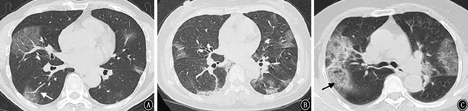

2组CT影像学基线资料比较见表2。A组支气管血管束及外周混合分布明显多于B组(χ2=32.705,P<0.001);B组胸膜下外周分布明显高于A组(χ2=13.268,P<0.001)。见图1、图2。

注:白色箭头示肺血管增粗;黑色箭头示"细网格"征

2组均以多肺叶受累为主,共检出52例(75.4%),其中A组的检出率100%(16/16)要高于B组73.5%(36/49),差异有统计学意义(χ2=5.306,P=0.021)。

早期征象最常见的是GGO,总检出率96.9%(63/65),A、B组GGO检出率无明显差异(χ2=2.420,P=0.120)。"细网格"征共检出32例(49.2%),A、B组的检出率分别为75%(12/16)和40.8%(20/49),差异有统计学意义(χ2=4.201,P=0.04)。以反晕征为主要表现的共检出8例(12.3%),A、B组的检出率分别为18.8%(3/16),10.2%(5/49),差异无统计学意义(χ2=0.608,P=0.436),但有1例危重症患者早期表现为多发性GGO和反晕征,48 h后病灶明显进展形成肺实变(图3)。病灶内血管影增粗,共检出47例(72.3%),A、B组的检出率分别为87.5%(14/16)和67.3%(33/49),差异无统计学意义(χ2=1.160,P=0.281)。

A组病灶边界较模糊(81.3%),而B组病灶边界清楚的居多(69.4%),2组病灶的边界比较差异有统计学意义(χ2=12.613,P<0.001)。

COVID-19的影像学早期征象以双肺多发GGO最为常见,这与SARS-Cov-2感染后引起肺泡壁的损伤、血管的充血和肺泡间隔的水肿有关[10]。本研究尝试对COVID-19患者的首次胸部HRCT进行分析后有如下发现。(1)病变在48 h内出现快速进展者的基线影像学特征表现为:病变多发、呈支气管血管束及外周混合分布、"细网格"影和病灶的边界模糊。这部分患者外周血淋巴细胞、CD4+T细胞减少,免疫功能低下,病灶不易局限,更易沿支气管血管束的轴向进展和蔓延[11]。而且由于淋巴细胞向靶器官迁移,导致局部的炎症反应明显使病灶的边界较为模糊。"细网格"征的检出率比较高,与SARS-Cov-2感染引起小叶间隔和小叶内间质增厚有关。(2)非快速进展者的基线影像学特征表现为:外周胸膜下外周分布的GGO、病灶边界清楚的多见。最常见分布区域的是两下肺基底段和背段,这是由于下肺和外周胸膜下区肺小叶的血流和淋巴管网分布丰富,相应小叶间质的炎性反应也更明显[12]。COVID-19病变的进展模式为以肺小叶为单位向外融合扩展,受小叶结构阻挡故而表现为具有一定的边界。推测这部分患者局部炎症反应相对较轻,病灶具有一定的自限倾向。(3)"反晕征"的检出率较低,但是曾有1例早期以多发性支气管血管束分布"反晕征"为主要表现,后期发展为肺实变的危重型病例,不排除SARS-Cov-2感染继发机化性肺炎的可能,需要引起临床足够的重视[13]。"血管影增粗"征检出率高,该征象在近期COVID-19的相关文献中也有报道[14,15],并且发现增粗的血管走行僵硬,边缘欠光整,考虑与病毒侵犯血管内皮细胞和肺泡毛细血管网,引起的血管炎有关[16]。但这两个征象与病灶的进展模式无明显相关性。